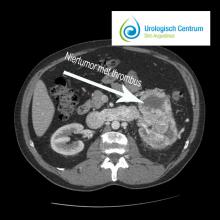

CT scan van het abdomen (Nierkanker)